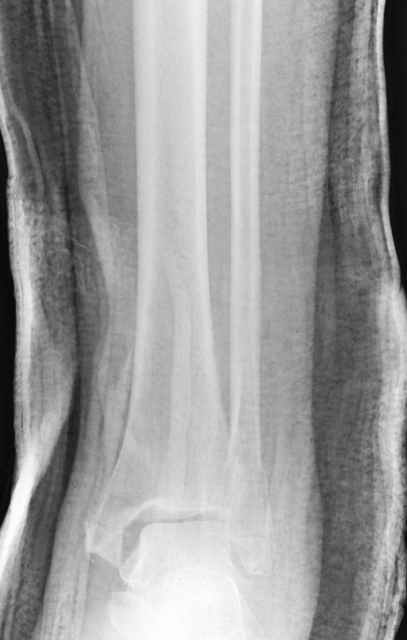

Дистракция в аппарате или на вытяжение результат - лигаментотаксис, посмотреть бы, как сегодня расположены отломки.